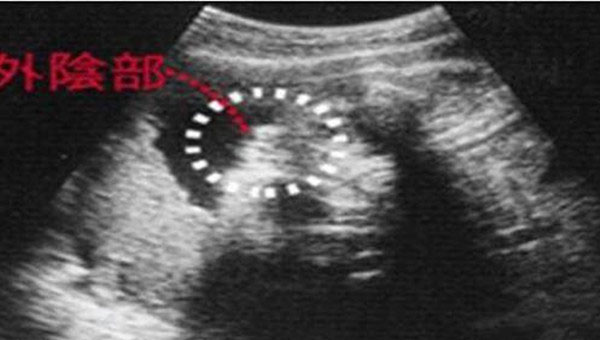

女宝宝从b超图中看到的影像,两腿中间有三条白线标志,这是女孩的外生殖器特征,也就是女宝宝的小***。

男宝宝从b超图中看到的影像,两腿中间有小亮点或小突起,这是男孩的外生殖器特征,也就是男宝宝的小JJ。